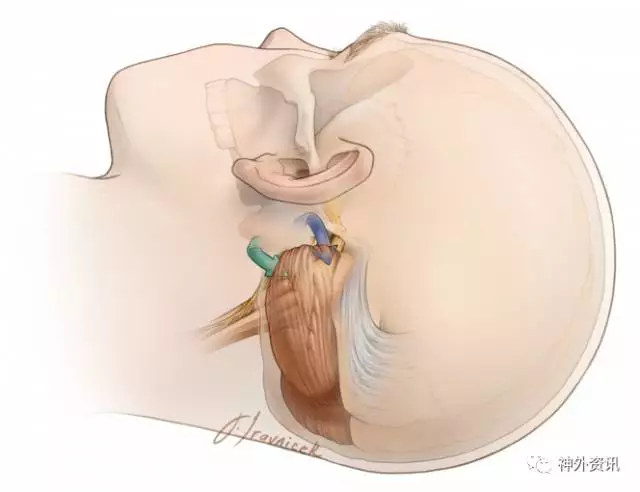

图6.到达桥小脑角的手术通道及方向:微血管减压术应用于三叉神经痛的手术入路(小脑上裂入路-蓝色箭头),和用于面肌痉挛、舌咽神经痛的手术入路(小脑下外侧入路和绒球下入路-绿色箭头)如上图所示。应避免向内侧牵拉小脑,因为这牵拉方向于听神经平行,增加了听力丧失的风险。